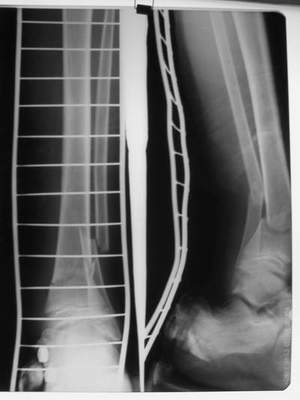

Вытяжение

|

Фиксация

в гипсе